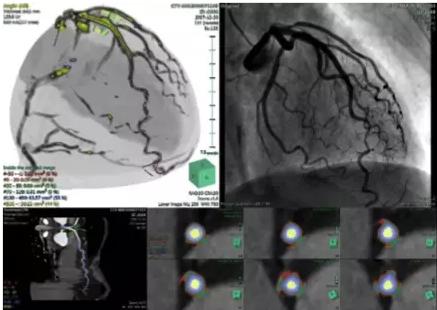

ANYTHINK 经导管主动脉瓣膜置换术分析系统